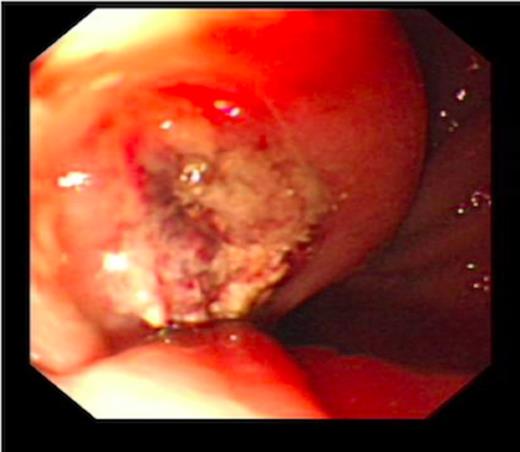

An endoscopy performed four years post-operatively demonstrated two atypical acute gastric ulcers in the distal stomach (figure 1), which were treated with a heat probe (figure 2). Two days later she presented as an emergency in hypovolaemic shock following a large volume haematemesis (haemoglobin of 40g/l). An urgent upper gastrointestinal endoscopy revealed a visible vessel at 35 cm forming part of an expansive mass within the gastric conduit. EUS demonstrated a heterogeneous mass indenting the gastric conduit, containing a strong Doppler signal (figure 3). An urgent computerised tomography (CT) angiogram revealed a Type-A thoracic aortic aneurysm with an enteric fistula (figure 4). The saccular aneurysm of the thoracic aorta was embedded in the gastric conduit. A 28x16cm Valiant® (Medtronic Ltd, Minneapolis, USA) stent was placed in the descending thoracic aorta with good occlusion of the aneurysm. The patient made an excellent recovery and was discharged on the seventh day post stenting.

Erosion of the gastric conduit by highly acidic gastric contents may also predispose to fistula formation (3). Gastric erosion and ulceration into both the aorta and pericardium from the intra-thoracic portion of the stomach has been reported post oesophagectomy. A reduced blood supply to the gastric conduit may predispose to gastric erosion. It is further proposed that chronic infection of these gastric ulcers may be a contributory factor. Pathological sections of aorta-oesophageal fistula have shown a granulomatous type inflammation suggestive of mycotic infection complicating ulceration (3). Indeed this may well have been the cause of the fistula in the case report we have described. An endoscopy performed two days prior to the presentation of the aorto-oesophageal fistula showed two acute atypical looking gastric ulcers.